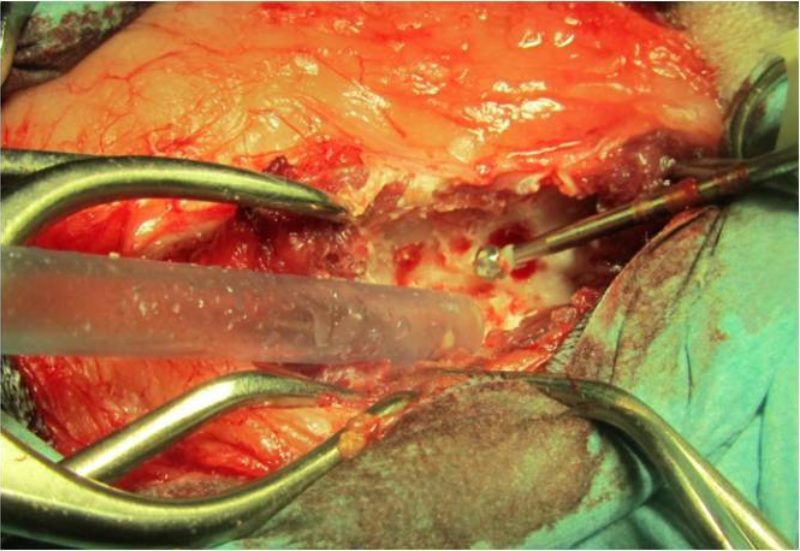

Die vor der Narkose durchgeführte Blutuntersuchung ergab keine Abweichungen von den Normalwerten. Die Röntgenbilder der Knie- und Hüftgelenke waren unauffällig. Bei der seitlichen Aufnahme der Lendenwirbelsäule fiel ein verengter und unruhiger Zwischenwirbelspalt zwischen dem 6. und 7. Lendenwirbel auf (Bild 1). Es wurde der Verdacht auf eine Bandscheibenerkrankung in diesem Bereich geäußert und den Besitzern eine weitere Abklärung mittels Computertomographie empfohlen. In der computertomographischen Untersuchung der Wirbelsäule konnte zwischen dem 6. und 7. Lendenwirbel in den knöchernen Wirbelkanal sowie in das linke Nervenaustrittsloch vorgefallenes Bandscheibenmaterial nachgewiesen werden (Bild 2 und 3). Dieses verursachte eine Kompression des Nervengewebes. Dieser Druck des vorgefallenen Bandscheibenmaterials auf das Nervengewebe war ursächlich für die hochgradige Schmerzhaftigkeit.